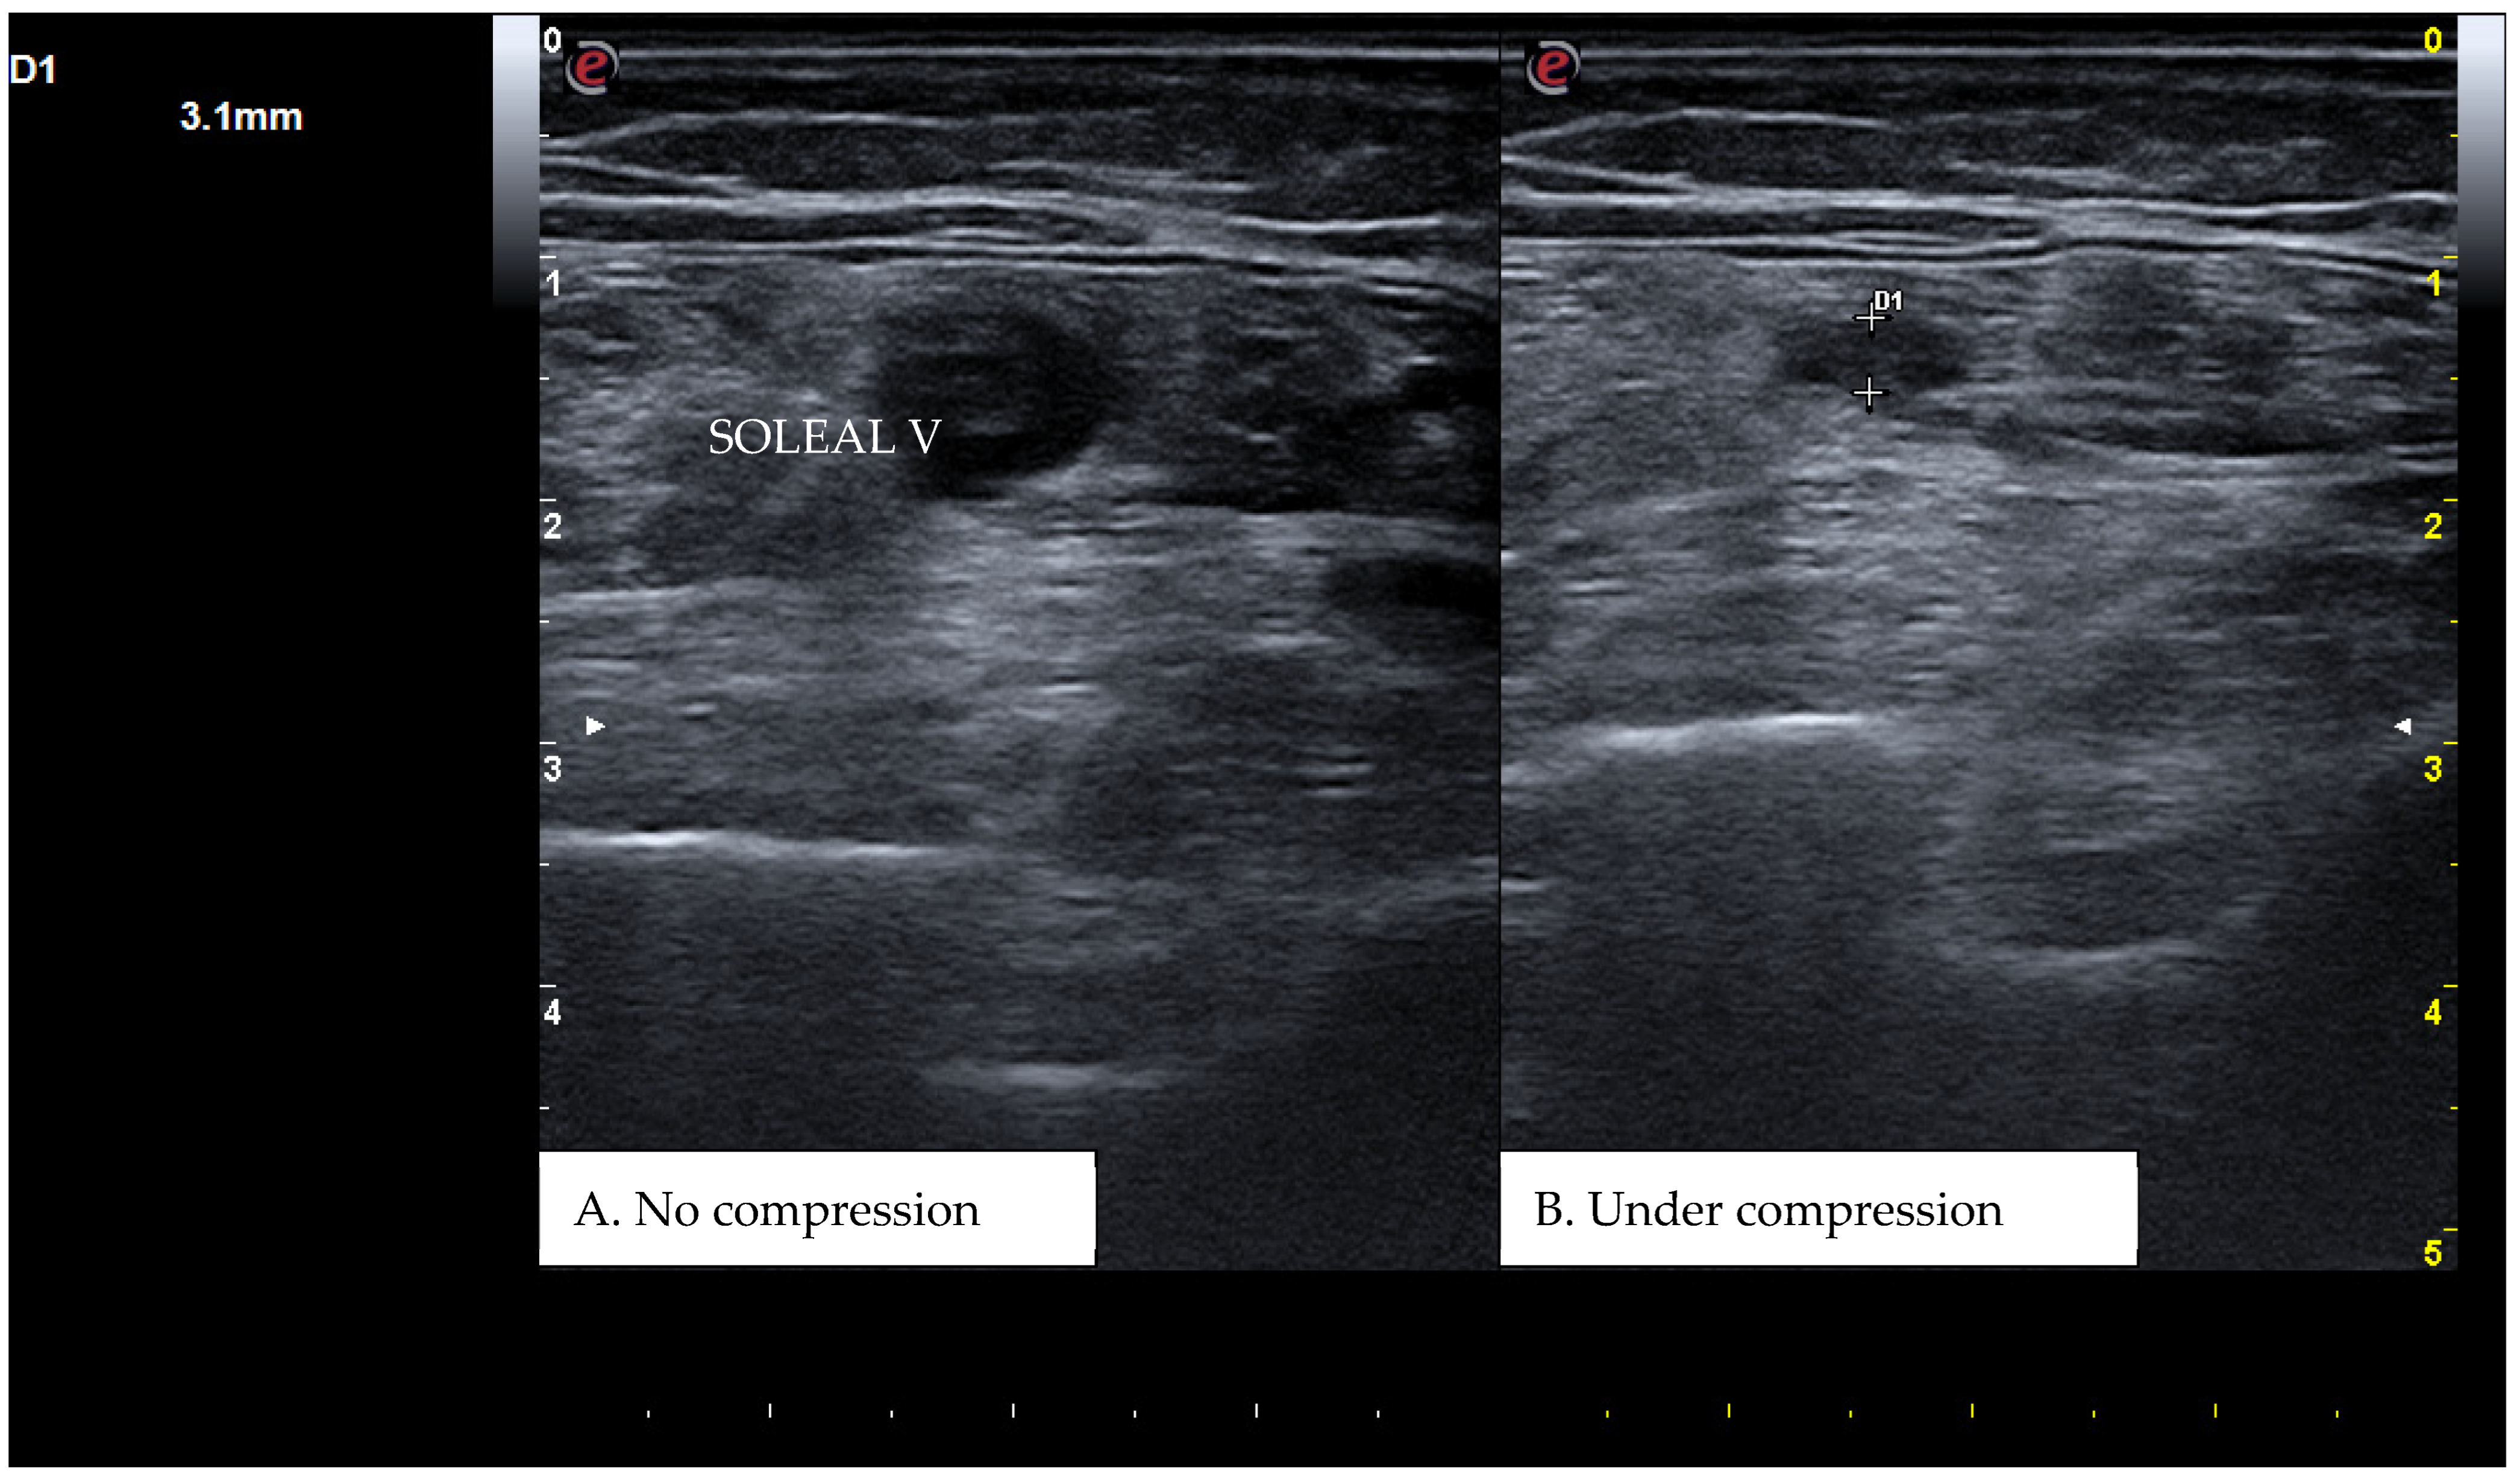

Figure 4. A real example of soleal vein thrombosis at the level of the right distal popliteal region. D1 shows the residual diameter of the non-compressible vein (i.e., the maximum diameter of the relative venous thrombus).

CUS is a diagnostic technique primarily designed to find DVT by checking the veins’ compressibility with the principle that healthy veins are normally compressible and would collapse under the pressure of the ultrasonographic probe. In the case of the presence of a venous thrombus, the vessel would not be able to collapse under such pressure [8,9]. Linear high-frequency transducers are generally used for CUS as they best visualize leg veins [10]. The ultrasound machine settings must be adjusted carefully in order to limit possible operator-related bias. Important elements to be considered in this setting include gain, focus, and time-gain compensation. Gain adjustment regulates image brightness, focus optimization sharpens the image to the desired depth, and time-gain compensation enhances the visibility of subtle echoes, ensuring uniform image quality [10,11]. The transducer partially compresses the vein, which creates an echogenic response. In normal veins, this technique should fully compress the lumen [9]. However, with thrombosis present, the vein does not collapse enough, which causes a non-continuous echogenic line [12]. While the femoral veins are usually well identified in the groin and thigh areas, to facilitate better visibility of the popliteal veins, the patient may lie in a supine position with the leg slightly abducted to relax the muscles or, alternatively, in a prone position [9]. Real-time B-mode and Doppler imaging are both valuable tools in this process. B-mode imaging can find incomplete vein collapse during compression [13,14]. Doppler imaging can show the thrombus or find a complete lack of flow in the lumen [9]. As such, CUS for DVT diagnosis involves evaluating direct signs like the presence of a non-compressible echogenic line suggesting a thrombus, as well as indirect signs like changes in vein compressibility and thrombus echogenicity [6,7]. In addition, evaluation of flow patterns and flow response during augmentation maneuvers may refine the diagnostic examination, although their implementation requires more advanced training and skills than simple CUS [7]. Clinicians should assess a spectrum of veins, including the external iliac, common femoral, superficial and deep femoral, popliteal, tibial, peroneal, gastrocnemial, and soleal veins, as well as the junctions with the great and small saphenous veins, representing the superficial systems [15]. Challenges exist in visualizing the iliac veins, especially in obese patients, yet phasic flow in the femoral veins can be indicative of DVT status, particularly for excluding iliac vein thromboses [16]. This comprehensive approach is standard in differentiating healthy veins, which should collapse and enlarge with augmentation maneuvers, from those with thrombosis, which show impaired response to pressure and flow changes [12,17]. Figure 1, Figure 2, Figure 3 and Figure 4 show real examples of DVT affecting different sites of the lower limb deep venous system, diagnosed through a CUS modality.